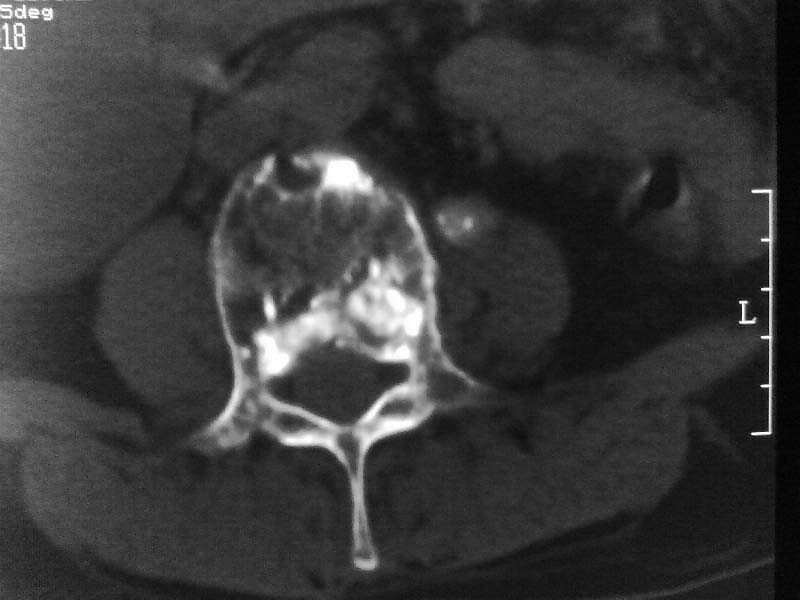

定位相示l2呈楔形改变(ct示陈旧性骨折改变,图像未传),l4.5椎体融合,以下是l4.5ct平扫.请各位看看,

考虑结核(有破坏、硬化及死骨)。

1、三四椎体结核,2、水平骶椎。

1、l1压缩性骨折(陈旧性)。

2、l3、4椎体结核。

就是腰1压缩性骨折,腰3\\4椎体结核(融合),水平骶椎.

支持 l1椎体陈旧性压缩性骨折;l3、4椎体结核(融合);水平骶椎。